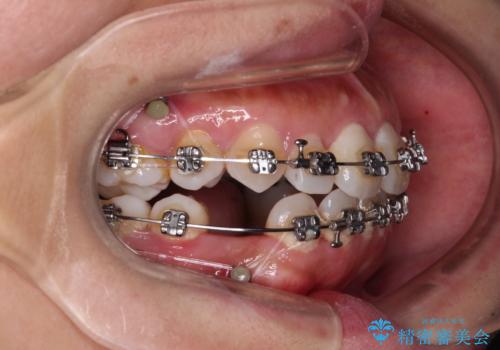

- 矯正装置

- メタルブラケット

- 2年9ヶ月

バランスを取るために右下と左上の小臼歯を1本ずつ抜歯し、移動のための固定源としてアンカースクリューを利用してワイヤー装置による矯正治療を行うこととしました。

骨格的な左右差があり、上下正中をぴったり合わせることは難しく、奥歯の咬み合わせの調整にも時間がかかりましたが、きれいに整えることができました。